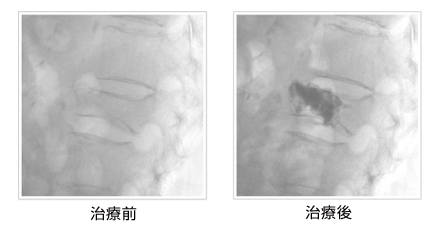

左は骨セメントを注入する前の写真。

右は手術した後の写真。注入したセメントは黒く映っている。

(写真提供:聖マリアンナ医科大学病院滝滝澤謙治教授)